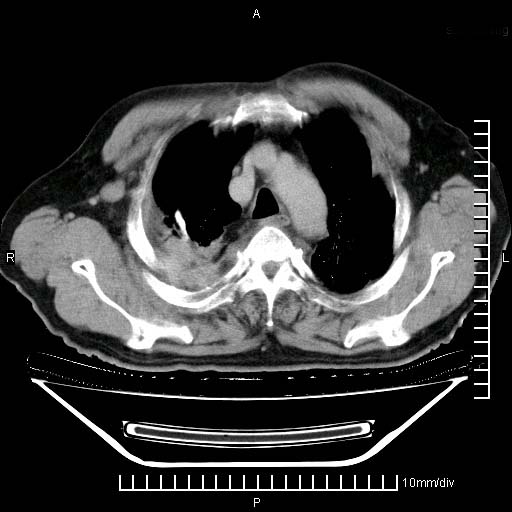

1)两肺继发性肺结核。2)右侧胸膜增厚+少量胸腔积液。